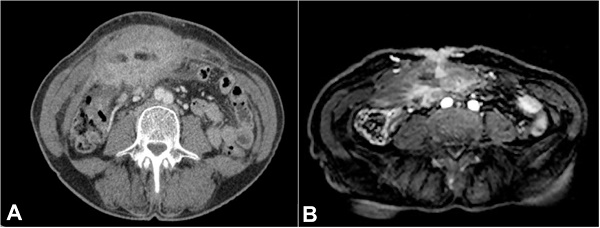

The contrast-enhanced computed tomography (CT) (Figure 1A) showed a heterogeneously enhanced solid mass (17,5 x 12 x 6 cm) involving the colonic hepatic angle and the proximal transverse colon with effaced limits, invading the muscles of the abdominal wall. No evidence of regional or distant lymph node disease, and no pulmonary or hepatic lesions.

A month and a half later, she was hospitalized under the care of the multidisciplinary group of soft tissue tumors. At this time, she presented a palpable erythematous periumbilical lesion. At this time, the abdominal magnetic resonance imaging (Figure 1B) identified a similar image depicted at the CT along with the involvement the anterior abdominal wall including the skin.